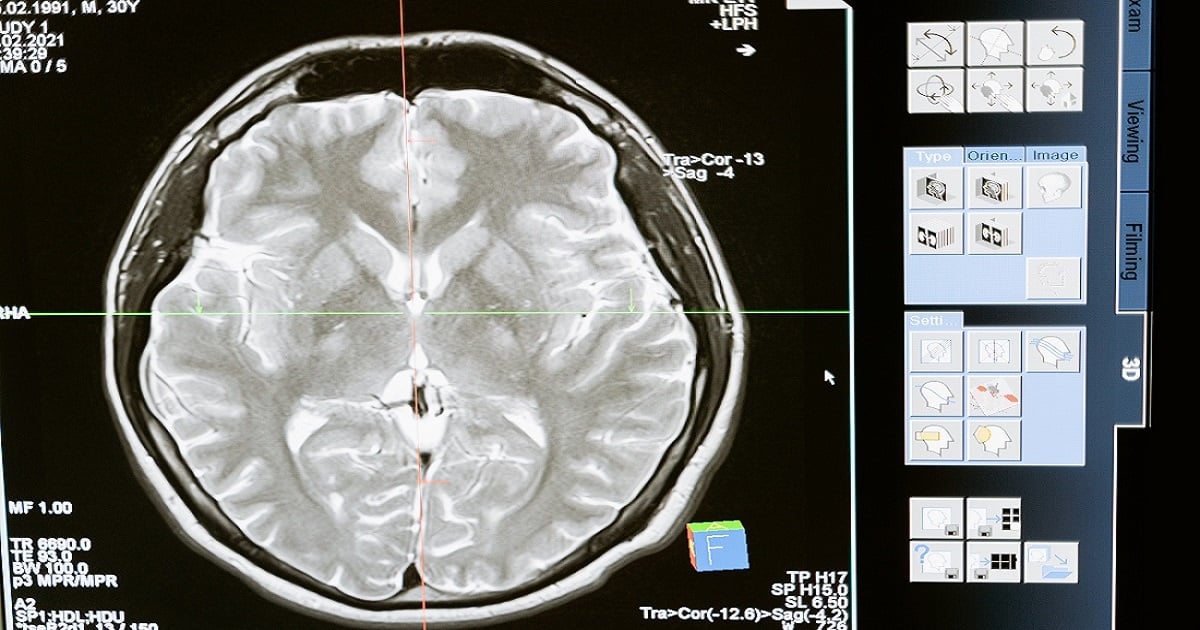

There are many different types of medical imaging techniques, which use different technologies to produce images for different purposes, for example, radiography, magnetic resonance imaging, ultrasound and tomography, depending on the physical nature of the waves employed and the method of image capture. There is no single imaging technology which is superior to the rest as each has its own advantages and disadvantages.

Research into the application of medical images is usually the preserve of radiology and the medical sub-discipline relevant to medical condition or area of medical science (neuroscience, cardiology, psychiatry, psychology, dentistry, etc.) under investigation. Many of the techniques developed for medical imaging also have scientific and industrial applications. One of the most exciting areas currently under research is the application of artificial intelligence (AI) to medical imaging.